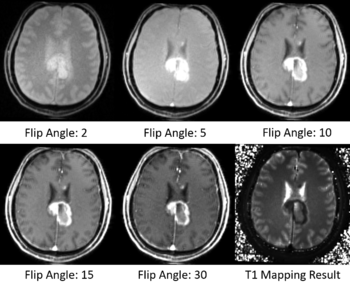

| − | [[File:T1_Mapping_Result_Sample.png| | + | [[File:T1_Mapping_Result_Sample.png|350px|thumb|left|Sample Results of T1 Mapping]] |

T1 mapping estimates effective tissue parameter maps (T1) from multi-spectral FLASH MRI scans with different flip angles. T1 mapping can be used to optimize parameters for a sequence, monitor diseased tissue, measure Ktrans in DCE-MRI and etc.

- Estimate effective T1 from multi-spectral FLASH MRI scans with different flip angles

- Test the Slicer module on MGH Brain Tumor MR Data with multiple flip angles